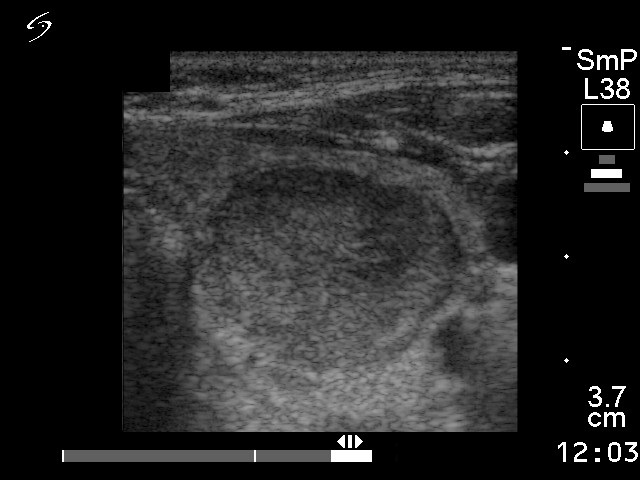

Ultrasonography disclosed a nodule with hypoechogenic, hyperechogenic and cystic parts in the right thyroid. The nodule presented a type 3 vascular pattern.